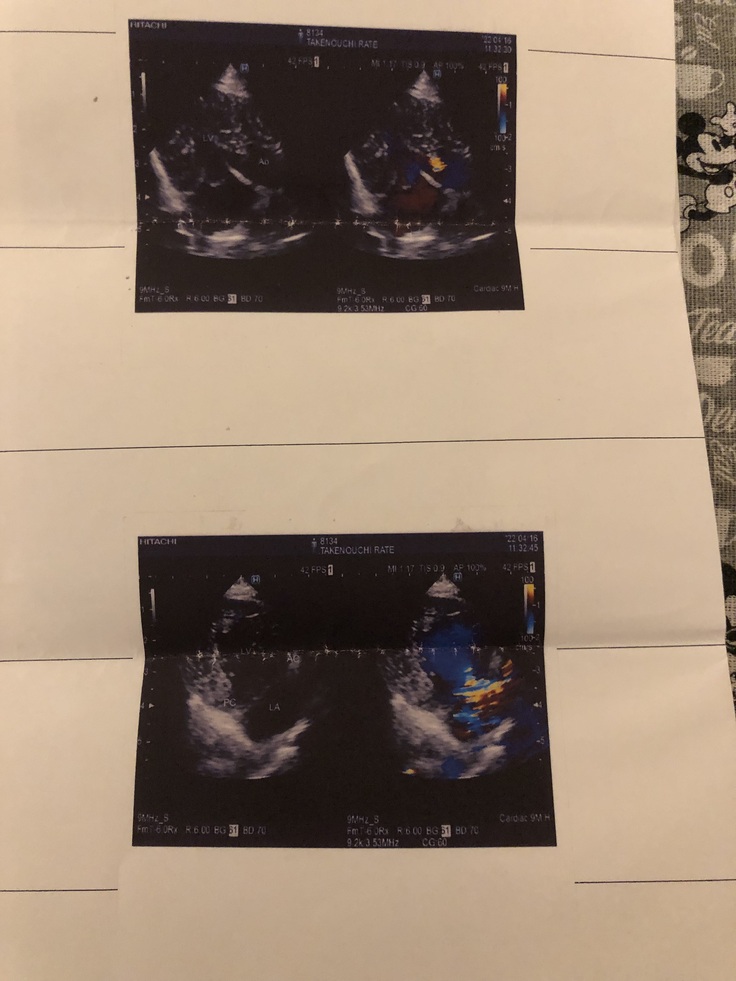

↑ANPは心不全の検査値です。上がってきています。

↑心肥大しています

↑カラーのところが逆流です。

かなり逆流があるため酸素交換がうまくいっていません。